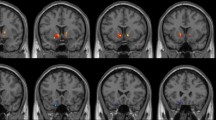

Compared with HCs, MADIs at Stage I demonstrated decreased ReHo values in the left superior parietal gyrus and left middle temporal gyrus, increased ReHo values in the left inferior temporal gyrus, right inferior temporal gyrus and right insula. MADIs at Stage I also exhibited decreased fALFF values in the right precentral gyrus, increased fALFF values in the left putamen and right putamen. (Table 2; Fig. 1)

Comparison of ReHo and fALFF values between MADIs at Stage I and HCs. MA: methamphetamine; MADIs: MA-dependent individuals; MADIs at Stage I: MADIs when they were abstinent from MA; HCs: healthy controls; ReHo: regional homogeneity; fALFF: fractional amplitude of low-frequency fluctuation. The significant differences were set at P < 0.005 (a minimum cluster size of 13 voxels, corrected by the AlphaSim program in REST software).